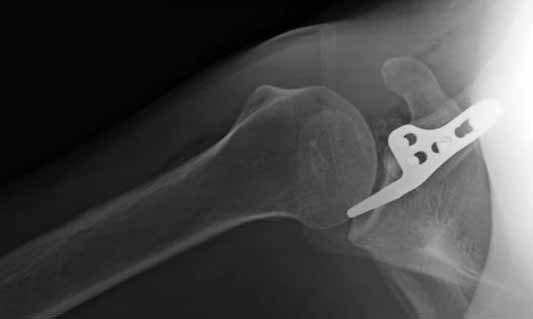

Вложение не в текстовом формате было извлечено…

Имя     : 3 Clavicle AC post op 2.jpg

Тип     : image/jpg

Размер  : 21914 байтов

Описание: отсутствует

Url     : http://weborto.net:8080/pipermail/ortho/attachments/20110623/6adf8600/attachment-0008.jpg